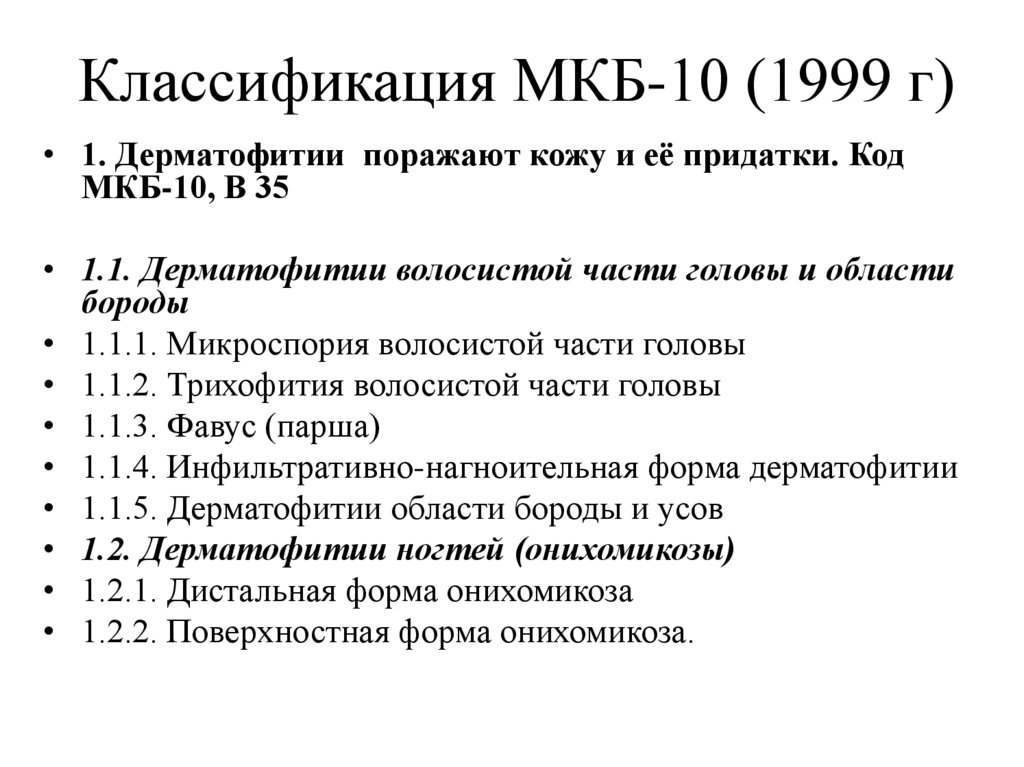

Код мкб 10 атерома головы

Код мкб 10 атерома головы 109 фото